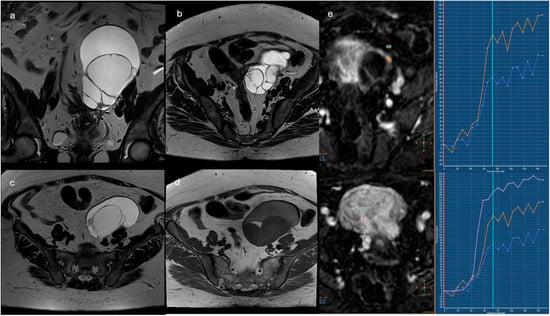

Pleuro-Pulmonary Extramedullary Plasmacytomas in Multiple Myeloma: A 15-Year Experience from a Tertiary Center

Background/Objectives: Extramedullary involvement in multiple myeloma represents an aggressive disease phenotype, associated with reduced survival and an unfavorable prognosis. Thoracic manifestations are rare and remain poorly characterized in the literature. Methods: We conducted a retrospective, single-center study at the Fundeni Clinical Institute, including patients diagnosed with multiple myeloma between February 2010 and February 2025. The study cohort consisted of 34 patients with infiltration of the pulmonary parenchyma, pleura, or the presence of myelomatous pleural effusion. Diagnosis was confirmed using a combination of imaging modalities (computed tomography or magnetic resonance imaging), cytological examination, immunophenotyping, and histopathological confirmation whenever feasible. Results: Out of a total of 2012 patients with multiple myeloma, the incidence of pleuro-pulmonary extramedullary involvement was 1.6%. The median age at diagnosis was 58 years. Pleuro-pulmonary disease was present at initial diagnosis in 26.5% of cases, while 73.5% developed it at relapse. The most common presentation involved combined pleural involvement and myelomatous effusion (70.6%). Adverse prognostic markers included elevated β2-microglobulin levels (in over 80% of cases) and increased lactate dehydrogenase (LDH) in approximately 50%. Cytogenetic abnormalities such as del(17p), t(4;14), t(14;16), t(11;14), and 1q gain were identified. The median overall survival (OS) from the diagnosis of pleuro-pulmonary extramedullary disease was 16 months, with a 2-year survival rate of 25%. No patient survived beyond 5 years. The median progression-free survival (PFS) was 9 months. Conclusions: Our findings confirm the aggressive clinical course and poor prognosis of these disease manifestations, mainly when they occur at relapse. In the absence of standardized treatment guidelines, individualizing therapy and accessing novel strategies may be essential for improving patient survival.